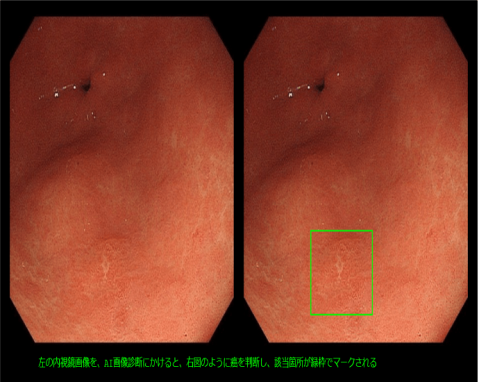

加藤さん:メイン事業は、内視鏡検査におけるAI診断支援ソフトウェア事業です。100を超える共同研究施設より医療データを収集し、胃がんの見逃しを減らすことを目標とした診断支援ソフトウェアの研究開発を行っています。第1弾の製品は2022年には承認を得て販売を開始する予定です。

加藤さん:胃がんも大腸がんも同じくらいの頻度で発生しますが、大腸がんは隆起するのに対し、胃がんは平坦なまま色だけ変わるという変異で見つけにくいのです。しかし、胃は栄養を吸収する臓器です。もしがんが広がり胃を全摘出した場合、栄養を摂り込めなくなるため、その後の生存率に関わります。

加藤さん:大腸ポリープに関しては国内・海外の企業での取り組みがあったのですが、胃がんは事例数が少なかったのです。また、AIで画像判定させたところ、胃がん発見の成績が良かったのも理由のひとつです。それらを含めて、AIで胃がんに挑戦しようということになりました。

加藤さん:医療データを集めるという部分に尽きると思います。医療AIという分野では、医療機関や医師と一般の人が関係を持つということが難しい。開発には医療データが必要ですが、個人情報保護の問題をクリアしつつデータ収集の協力を依頼しなくてはいけません。これは私たちだけではできないことなので、どうしても医療機関や医師に頼ることが多くなります。そこが一番の障壁でした。 次に、技術的な課題もありました。がんは人工物ではありません。一般的に生体培養はAIには難しいという技術的なハードルもあり、これまでの古い技術では不可能なように思えましたが、深層学習という新しい技術を使うことで手掛かりを掴めました。 また、医療機器をリリースするためには、多くの規制に対応する必要があります。審査の構造的な問題もあり、ベンチャーが挑戦するのは難しい課題でした。そこは医療機器開発経験がある優秀なスタッフを採用し対応しています。まだまだ多くの技術的及び薬事的な課題が残っていますが、これら多くの課題を一緒に解決してくれる優秀な方の当社へのジョインを期待しています。